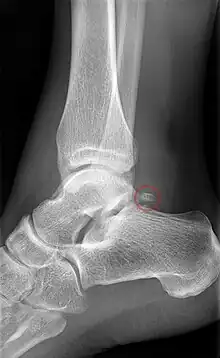

Accessory bones at the ankle mainly include:

- Os subtibiale, with a prevalence of approximately 1%.[14] It is a secondary ossification center of the distal tibia that appears during the first year of life, and which in most people fuses with the shaft at approximately 15 years in females and approximately 17 years in males.[14]

- Os subfibulare, with a prevalence of approximately 0.2%.[15]

Os trigonum (further described below) may also be seen on an ankle X-ray.